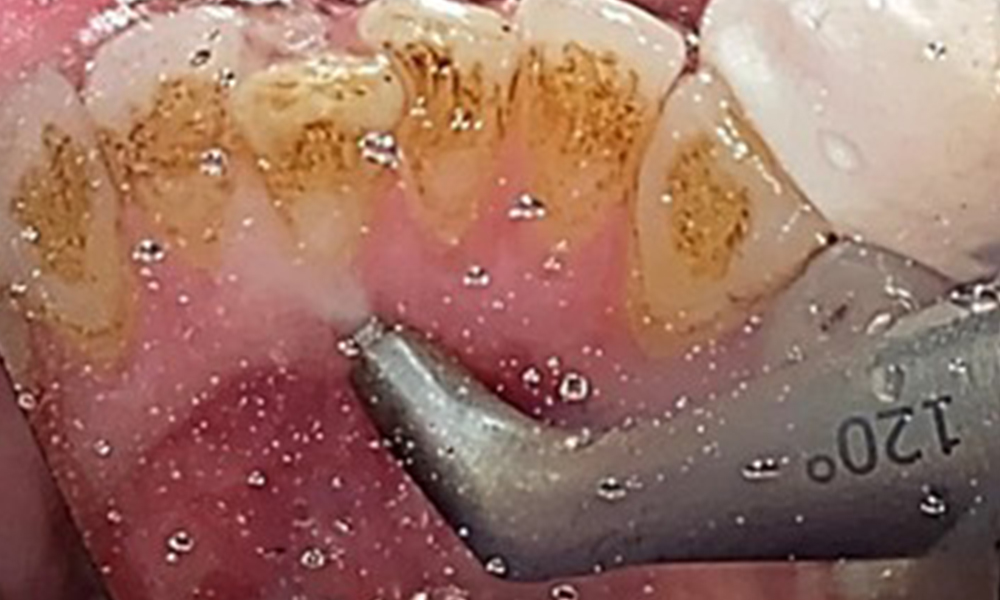

Поради иначе благоприятното общо медицинско състояние, нуждите, определени по време на оралния преглед, ще бъдат решаващи за лечението. От съществено значение ще бъде периодичното определяне на дълбочината на сондиране. Гингивалното кървене намалява при пушачите, поради което клиничната диагноза на пародонтита може да се постави само чрез сондиране (фиг. 7). Поставянето на изключителен акцент върху определянето на индексите на кървене може да замъгли съществуващ пародонтит или гингивит. (5)

Целта е да се контролира рискът от заболяване чрез отстраняване на супрагингивалния и субгингивалния биофилм. Инструментите трябва да бъдат подбрани въз основа на нуждите на пациента. Първо трябва да се отстранят зъбният камък и всички конкременти с помощта на ултразвукови и/или ръчни инструменти (фиг. 10).